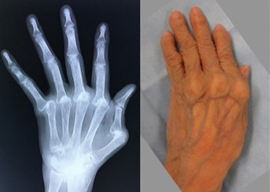

関節リウマチ

リウマチによる手・肘の変形に対する治療は一般的に難易度が高く、また習熟している施設は限られています。当院ではリウマチ手指や肘に対する人工関節手術を積極的に行い、良好な治療成績を得ています。また比較的若年の方で関節面が保たれている場合は可能な限り関節温存手術を行います。当院の担当医はリウマチ指の人工関節手術、人工肘関節手術、人工関節を用いない手指軟部組織形成術や肘関節形成術の経験も豊富です。人工関節は複数の種類がありますが、患者さんの状態に合わせて使い分けています。肩については、変形性関節症のところでも触れている、近年開発された肩の特殊な人工関節(リバース型)が導入されて以降、良好な成績が得られています。

人工手指関節手術前 -

手術後 -